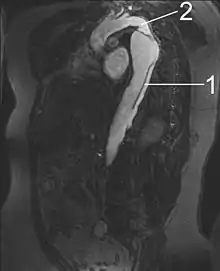

By separating a portion of the wall of the artery (a layer of the tunica intima or tunica media), a dissection creates two lumens or passages within the vessel, the native or true lumen, and the "false lumen" created by the new space within the wall of the artery.